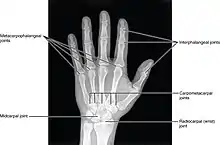

Articulation interphalangienne de la main

Les articulations interphalangiennes de la main sont les articulations qui unissent les phalanges de la main.

Chaque doigt, sauf le pouce, possède deux articulations interphalangiennes :

- une articulation interphalangienne proximale entre la phalange proximale et la phalange moyenne,

- une articulation interphalangienne distale entre la phalange moyenne et la phalange distale.

Le pouce n'a qu'une articulation interphalangienne entre la phalange proximale et la phalange distale.